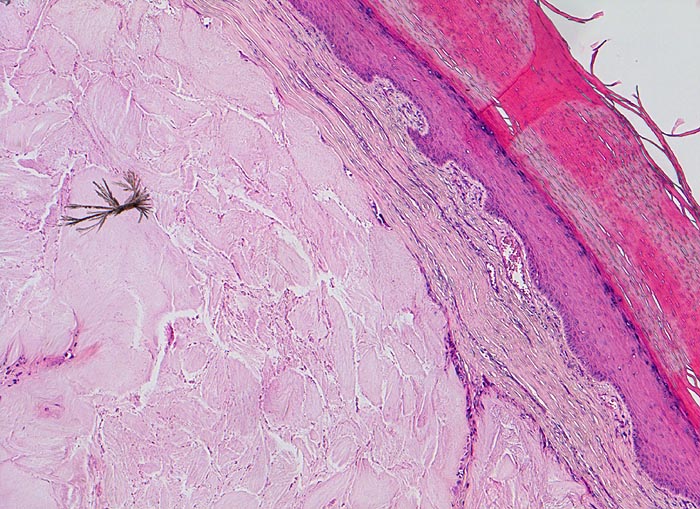

PathoPic – image database / PathoPic ID 5119 - Gichttophus

Gichttophus

Systemerkrankung/Immunpathologie

Haut

Stark verhornende Epidermis. Intradermaler Tophus bestehend aus amorphem eosinophilem Material und einzelnen bereits in der HE Färbung erkennbaren nadelförmigen Kristallen. Spärliches Entzündungsinfiltrat in der Knotenperipherie.

Rezidivierend geschwollenes und gerötetes Grosszehengrundgelenk. Schmerzattacken, teils abhängig von Nahrungs- und Getränkeeinnahme.